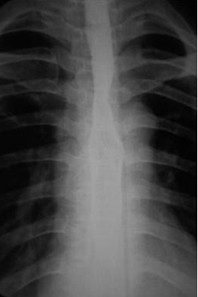

女,51歲,以“進(jìn)行性吞咽困難1年”為主訴于2007年2月19日入院。鋇餐造影、胃鏡示食管上段占位性病變,確診為食道鱗癌(圖1),拒絕手術(shù),行放療+今又生治療。食道鏡下瘤內(nèi)注射今又生,1×1012VP/次/周×6,放療在今又生注射3 d后開始,采用常規(guī)分割三野等中心照射,劑量65cGY。治療結(jié)束后4周,食管X線、胸部CT顯示腫瘤完全消退(圖4-5)。

放療結(jié)束4周后